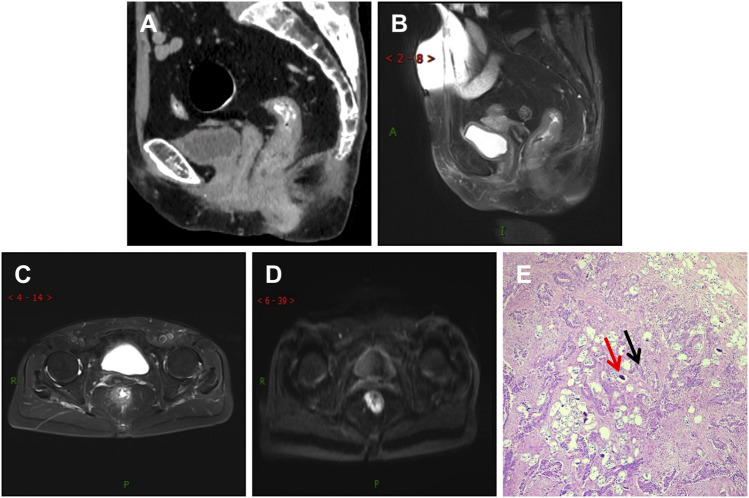

本研究旨在检查和比较有血吸虫病和无血吸虫病结直肠癌(CRC)患者的临床、放射学和病理学数据,并揭示伴有血吸虫病的结直肠癌的独特特征。这项回顾性研究基于从 341 名手术后和病理诊断为 CRC 的患者收集的数据。其中,101 名患者(A 组)被诊断为合并血吸虫病的结直肠癌(CRC-S),240 名患者(B 组)被诊断为未合并血吸虫病的结直肠癌(CRC-NS)。两组患者的临床数据、基于影像学的 TNM 分期、淋巴结转移、神经侵犯、血管癌栓和组织病理学分化情况进行了比较和分析。通过卡方检验发现,CRC-S(A 组)和 CRC-NS(B 组)患者的性别分布存在显著差异,P 值为 0.043,χ2 = 4.115。两组间 TNM 分期的总体分布存在差异(P = 0.034,χ2 = 6.764)。经配对比较,T3 期的差异有统计学意义(P = 0.005,χ2 = 10.626)。经过配对比较,分化良好的腺癌与中度和分化不良的腺癌之间的差异有统计学意义(p p > 0.05)。在 101 例 CRC-S 患者中,87 例(86%)在 CT 成像中显示出线性钙化。CRC-S 患者以男性为主,肿瘤分期多为中期,肿瘤分化程度高,恶性程度低。CT 成像可帮助识别血吸虫沉积的肿块和线性钙化。核磁共振成像可早期明确TNM分期,确定是否存在淋巴结转移、神经和血管侵犯。

This study aims to examine and compare clinical, radiological, and pathological data between colorectal cancer (CRC) patients with and without schistosomiasis and uncover distinctive CRC characteristics when accompanied by schistosomiasis. This retrospective study is based on data collected from 341 patients diagnosed with CRC post-surgery and pathology. Of these patients, 101 (Group A) were diagnosed with colorectal cancer co-occurring with schistosomiasis (CRC-S), while 240 patients (Group B) were diagnosed with colorectal cancer without concurrent schistosomiasis (CRC-NS). Both groups were compared and analyzed based on their clinical data, imaging-based TNM staging, lymph node metastasis, nerve invasion, vascular cancer thrombus, and histopathological differentiation. A Chi-squared test revealed a significant difference in gender distribution between the patients with CRC-S (Group A) and CRC-NS (Group B), with a p -value of 0.043 and χ2 = 4.115. Specifically, a higher incidence rate was observed among males in Group A. There was a difference in the overall distribution of TNM staging between the two groups (p = 0.034, χ2 = 6.764). After pairwise comparison, a statistically significant difference was observed in the T3 stage (p <0.05). The proportion of the T3 stage in Group A was significantly higher than that in Group B, indicating certain advantages. There was a difference in postoperative histopathological grading between the two groups (p = 0.005, χ2 = 10.626). After pairwise comparison, a statistically significant difference was observed between the well-differentiated adenocarcinoma and the moderately and poorly differentiated adenocarcinoma (p <0.05), with a higher proportion of welldifferentiated patients in Group A compared to Group B. There was no significant difference in age, lymph node metastasis, nerve invasion, and vascular invasion between the two groups of patients (p > 0.05). Among the 101 patients with CRC-S, 87 (86%) showed linear calcification on CT imaging. Patients with CRC-S are mainly male, with tumor staging mostly in the middle stage, high tumor differentiation, and low malignancy. CT imaging can help identify the presence of lumps and linear calcification indicative of schistosome deposits. MRI can early clarify TNM staging and determine the presence of lymph node metastasis and nerve and vascular invasion.